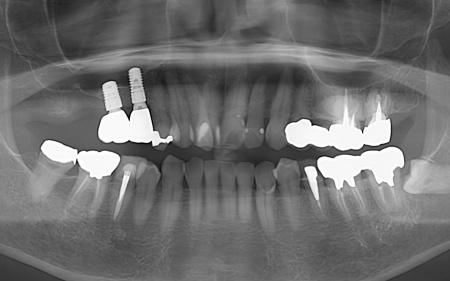

| カウンセリング・診断結果 | 拝見したところ、右上の歯には、欠損部位前後の歯を土台として橋を渡すように連結した被せ物「ブリッジ」が装着されていました。 しかし、土台となっている手前の歯(第2小臼歯)は歯根が割れており、同じく土台となっている奥の歯(第2大臼歯)は歯根の先に膿の袋ができる「根尖病巣(こんせんびょうそう)」が認められます。 さらに、ブリッジ部位の歯茎は腫れ、痛みもあるとのことでした。 かかりつけの歯科医院では、細菌感染を抑える薬を飲んだり、歯を少し削って噛み合わせを調整したりして様子を見ていましたが、口腔内の状態が改善せず、次は抜歯をする必要があると説明を受けたそうです。 また抜歯後に歯を補う方法のひとつにインプラント治療がありますが、患者様の場合は治療に必要な骨量が確保できないため難しいとされ、取り外し式の入れ歯になるとのことでした。 患者様はかかりつけ医からの説明が十分でないと感じていたため、当院にセカンドオピニオンで来院されています。 以上のことから、まずはブリッジ周辺の治療を行ったのち、欠損部を補う治療方法をしっかりと検討する必要があると診断しました。 |

| 行ったご提案 ・治療内容 | 痛みが出ているブリッジ周辺の治療として、ブリッジの土台となっていて、歯根が割れている手前の歯(第2小臼歯)は抜き、根尖病巣を発症している奥の歯(第2大臼歯)は、根管治療を行います。 根管治療とは、感染した神経を取り除いて、歯根内部を清掃・消毒する治療方法のことです。 抜歯と根管治療を行ったあとは、欠損部を補うために、2本のインプラントを埋入する方法を提案しました。 インプラントを埋入するために必要な骨量が足りない場合は、鼻の空洞(上顎洞)の粘膜を少しずつ押し上げて骨を増やす「ソケットリフト」を併用することもお伝えしています。 インプラント治療のメリット インプラント治療のデメリット それぞれの方法について丁寧にお伝えした結果、治療に同意いただきました。 まずは、右上手前の歯(第2小臼歯)を抜きました。 抜歯後は、インプラント治療を行うために、歯を支える骨(歯槽骨)の回復を待つ必要があり、最低でも6ヶ月を要します。 約2ヶ月後、インプラントと骨が結合したことを確認して、右上奥歯2本の仮歯を作製し、手前の歯槽骨が再生するまで経過観察を継続します。 約4ヶ月後、歯槽骨の再生が確認できたため、もう1本のインプラントを埋入しました。 当院のインプラント治療は、施術の安全性と長期的な使用を可能にすることを優先して治療を行うため、通常は抜歯後に歯槽骨の治癒を待ってからインプラントの埋入を行っています。 右上奥歯2本に仮歯が入り、噛み合わせが安定した状態になったため、根尖病巣を発症している右上奥歯の治療を開始します。 また、インプラントに装着する人工歯を作製する前に、歯科医院で歯を白くするオフィスホワイトニング治療を希望されたため、治療期間がやや長くなっています。 最後に、完成した人工歯を装着し、見た目や噛み合わせに問題がないことを確認して、治療を終了しています。 |

治療前

治療中